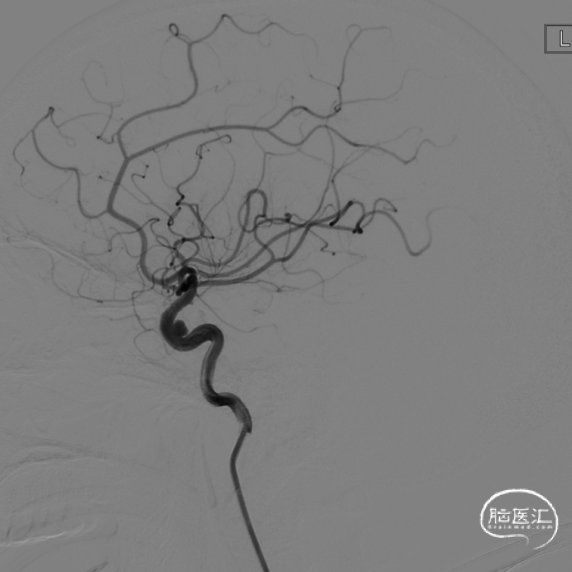

左侧颈内动脉眼动脉段动脉瘤,呈囊状,大小约6.42×5.31×2.65mm,瘤颈4.32mm,颈内动脉直径约4.66mm,瘤体指向内后外方。

患者多发动脉瘤,两侧动脉瘤均位于眼动脉段,首选介入栓塞治疗;考虑左侧动脉瘤体积大,部分位于海绵窦内,部分位于颅内,建议先治疗左侧眼动脉段动脉瘤,择期再治疗右侧动脉瘤。家属同意行介入栓塞治疗。